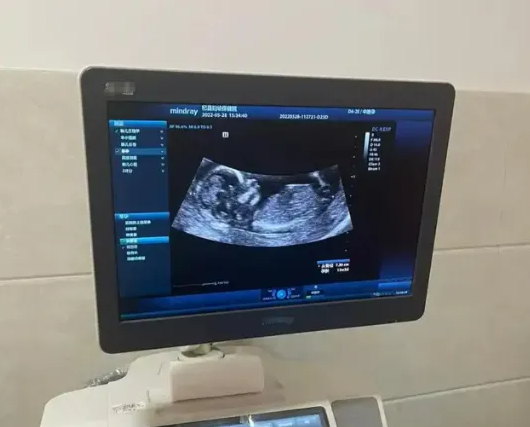

b超是孕妇在妊娠期间需要进行的一项检查,通过B超,医生可以了解胎儿各器官的发育情况,判断胎儿有无发育疾病,对于胎儿是否健康发育则有着重要的意义。

但B超本身并不是一项胎儿性别的鉴定技术,所以无论是B超检查图像,还是B超的结果报告单,都是不能判断胎儿是女儿还是儿子的,如果想要知道胎儿的性别,建议进行专业的胎儿性别鉴定。

其实孕早期通过B超单看胎儿性别并不准确,因为孕早期胎儿的生殖器尚未发育成型,这时候即使进行了B超检查,也基本不能看出胎儿的具体性别,误差率是比较大的,要等到怀孕4个月左右,胎儿的生殖器才会发育完全,这时候看男女的准确率会高一些。

B超单上其实是没有透露胎儿性别的数据的,因为国家禁止出于非医学目的探知胎儿性别,所以大家无论是在B超检查的影像中,还是B超检查结果单,医生都会刻意避免透露胎儿的性别,甚至会抹去一些关键部位,这就导致了B超单上根本就不可能有能证明胎儿性别的数据。